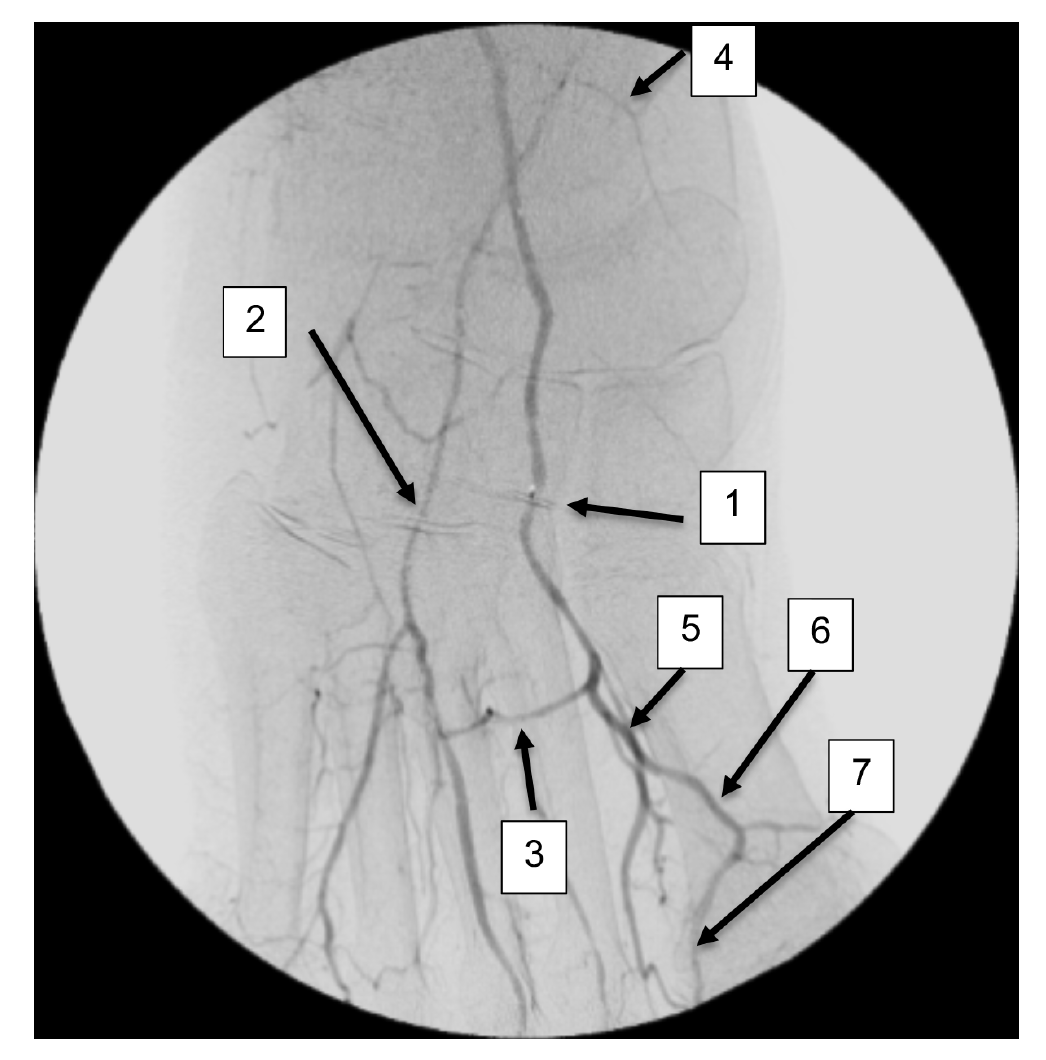

A right lower-extremity angiogram was performed using ultrasound guidance for antegrade access of the proximal superficial femoral artery (Figure 2A). Fluoroscopic acquisition demonstrated no significant disease in the superficial femoral artery (Figure 2B) and popliteal artery (Figure 2C), with no significant stenosis seen in the anterior tibial artery, PTA, and peroneal artery (Figure 2D). Pedal angiography demonstrated a complete pedal-plantar loop formed by the DPA and the lateral plantar artery (LPA) (Figure 2F).

However, the entirety of the medial plantar artery (MPA) distribution was chronically occluded shortly after take-off (Figure 2E and Figure 2F). Super-selective angiography revealed chronic total occlusion of the medial branch of the first common plantar digital artery arising from the first plantar metatarsal artery (Figure 2G). Angiography also revealed an occluded accessory branch arising medially from the superficial branch of the MPA.

The anatomy of the arteries supplying the hallux is complex, with variants being common. In this patient, an atypical accessory branch arising from the superficial branch of the MPA was present. While the arterial anatomy of hallux-supplying arteries and its corresponding variants are not readily discussed in recent literature, certain textbooks do depict an accessory branch arising from the superficial branch of the MPA.2 The accessory branch of this patient, in particular, communicated with the first dorsal metatarsal artery arising from the DPA (Figure 2F) and the superficial branch of the MPA communicated with the medial branch of the first common plantar digital artery arising from the LPA (Figure 4C). In general, using the angiosome concept, the blood supply to the hallux consists of 3 main avenues: (1) the first dorsal metatarsal branch arising from the DPA; (2) the plantar digital arteries arising from the first plantar metatarsal artery, which is a branch of the LPA; and (3) the superficial branch of the MPA.3,4 The latter 2 sources of blood supply were absent in this case.